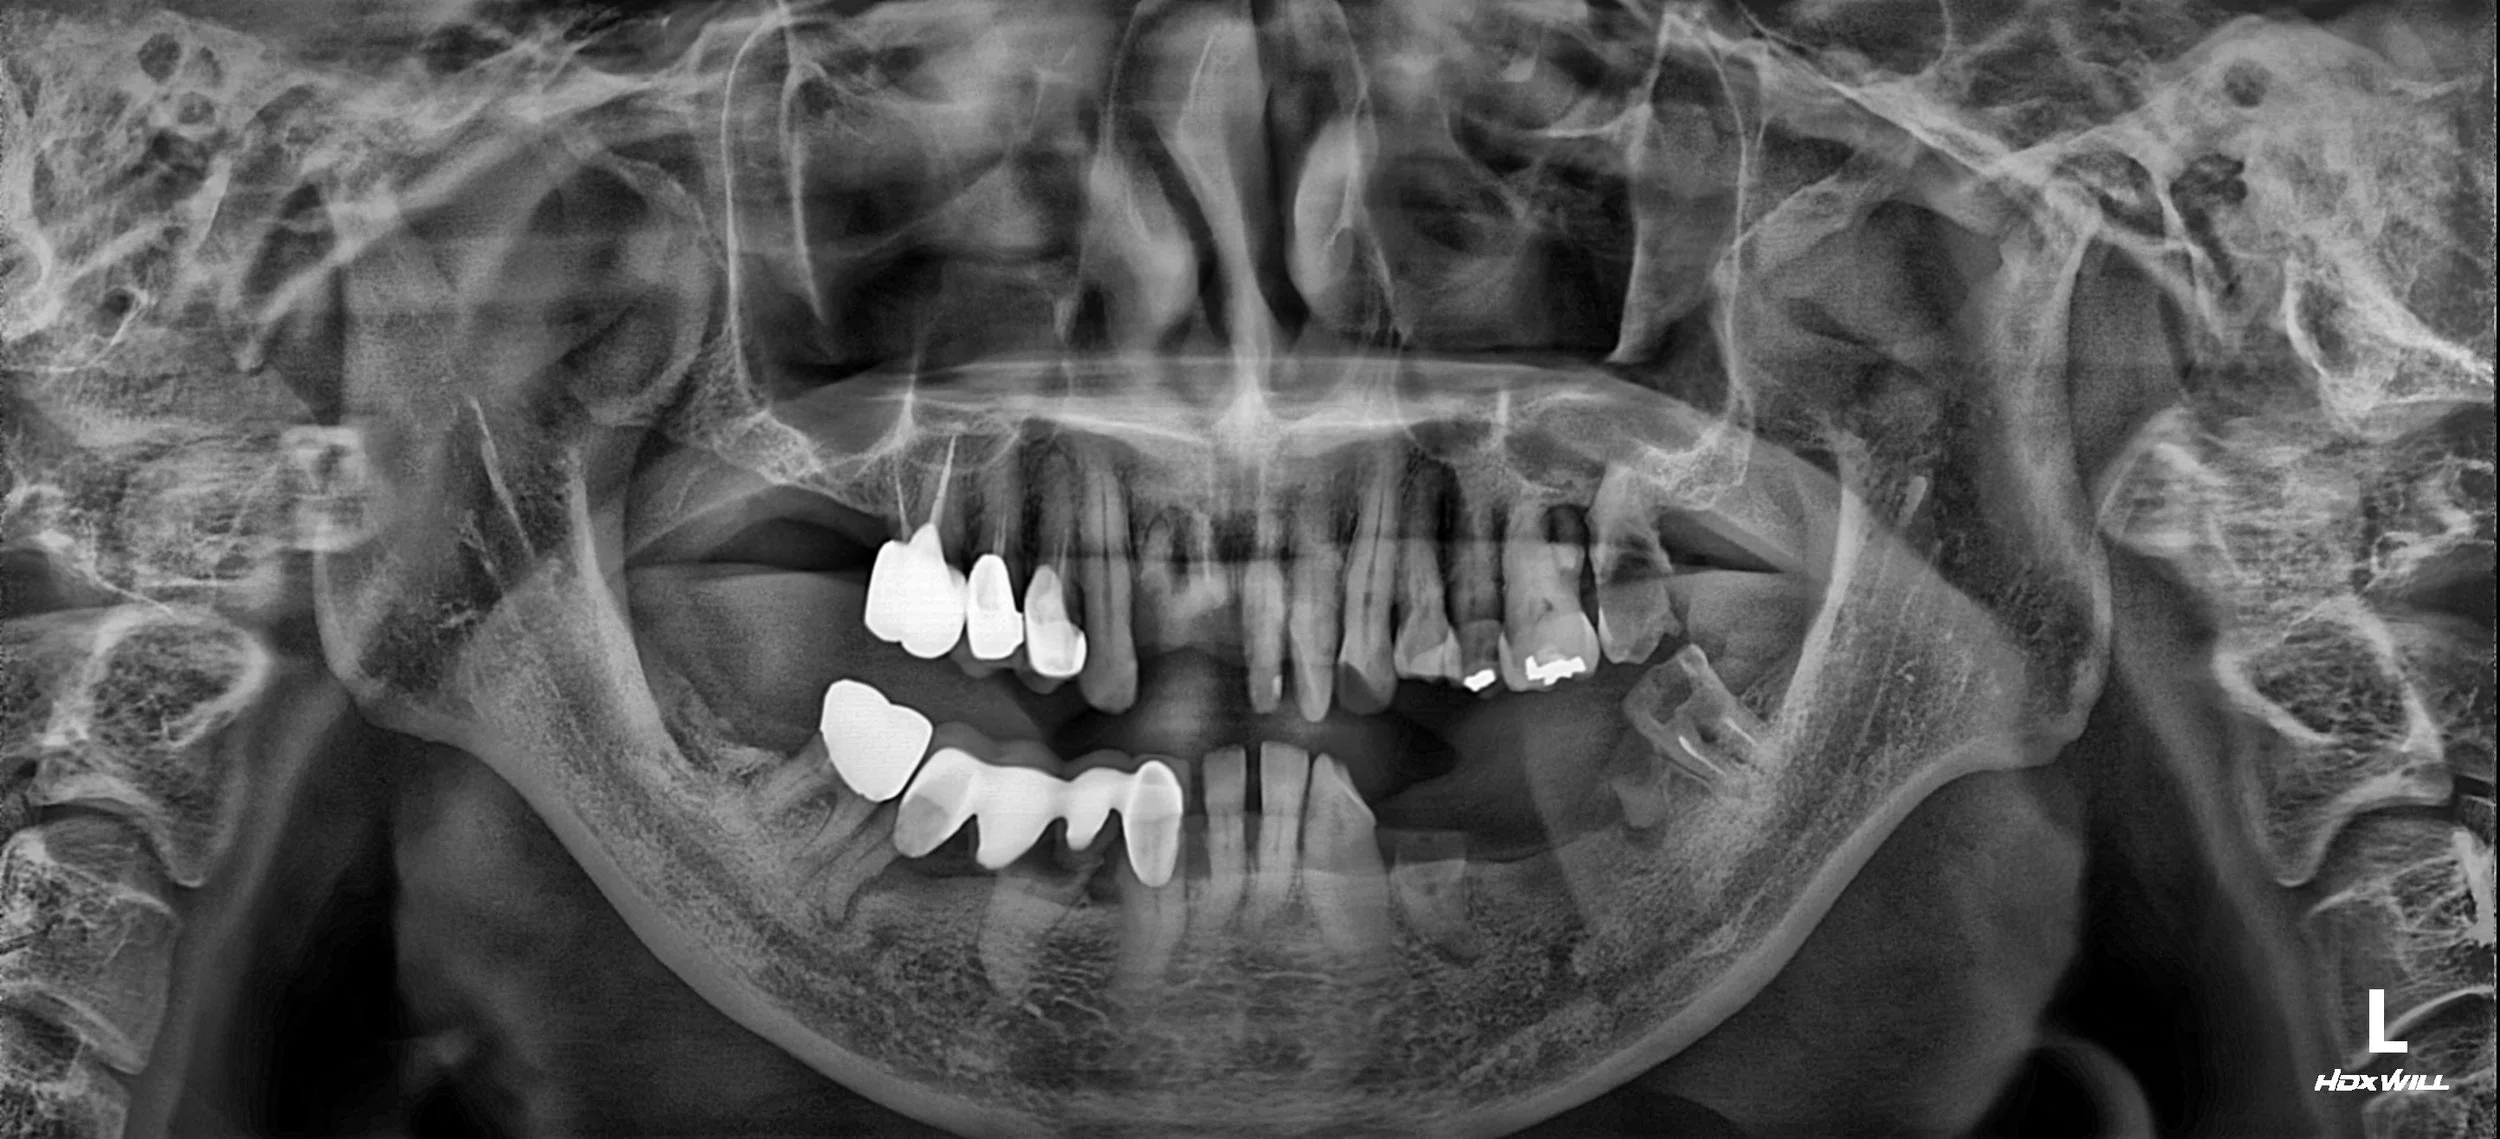

OPG - BEFORE

The patient presented with a collapsed occlusion and mandibular instability,

associated with long-standing unilateral mastication and facial asymmetry.